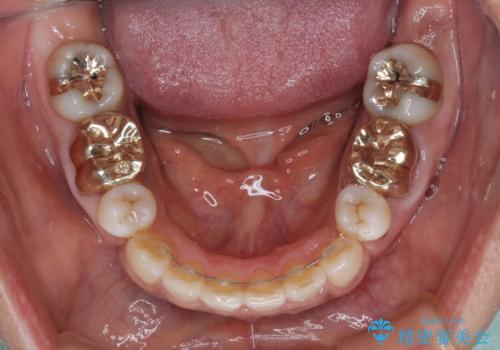

- 矯正治療後に、下顎奥歯の銀歯をすべてゴールドにすることを希望された患者様です。

セラミッククラウンやセラミックインレーによる補綴治療も提案しましたが、お友達にゴールドを自慢したいとのことで、ゴールドクラウンとゴールドインレーにて処置することとしました。

ゴールドは「白い歯」ではありませんが、銀歯の金属色とは異なり、非常にきれいな色合いが特徴です。

もちろん、適合が極めて良いという圧倒的メリットもゴールドクラウンやゴールドインレーの特徴です。